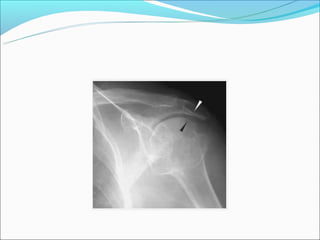

AR – Migração axial da cabeça do

fêmur

AR – Derrame articular